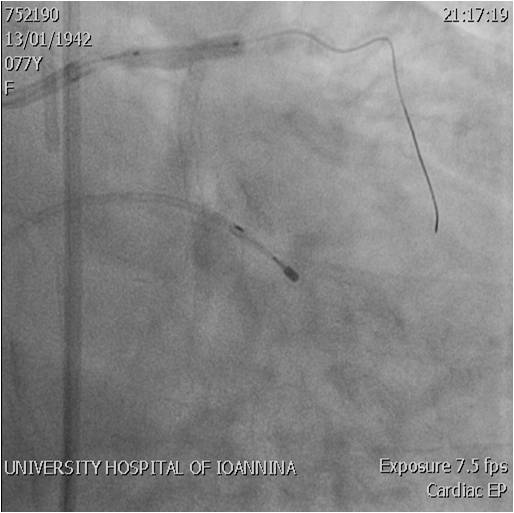

- Stenting mid LCx

- Stenting LM-LCx

- Stent crush

- 1st Kissing balloon

post-dilation - Stenting LM-LAD

- 2nd Kissing balloon

post-dilation

- Τελικό αποτέλεσμα αγγειοπλαστικής LM/LAD/LCx